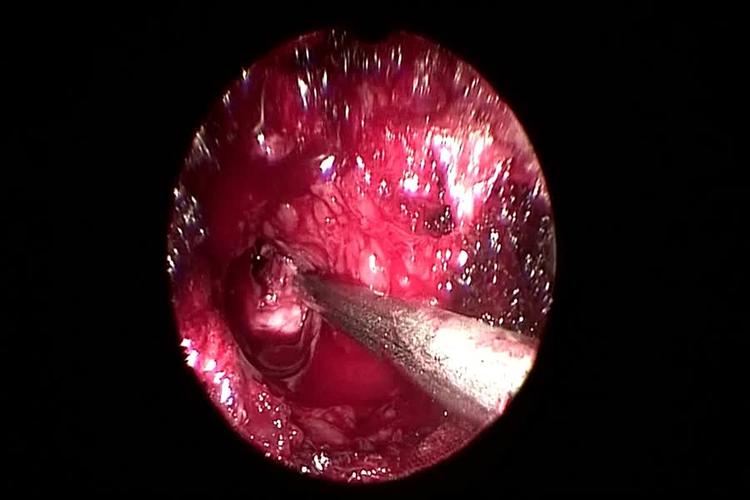

骨二科邓强主任团队杨镇源副主任医师完成甘肃省首例镜下纤维环缝合术

内窥镜辅助下腰椎髓核摘除术 纤维环缝合术

纤维环缝合术